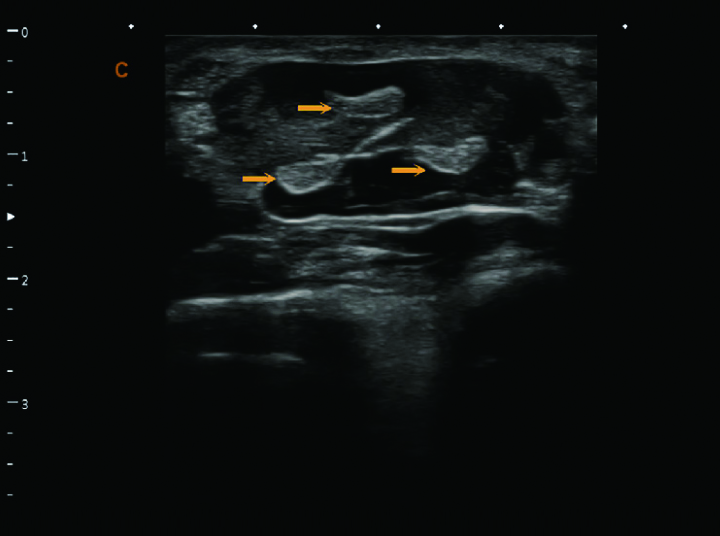

腕腱,B模式